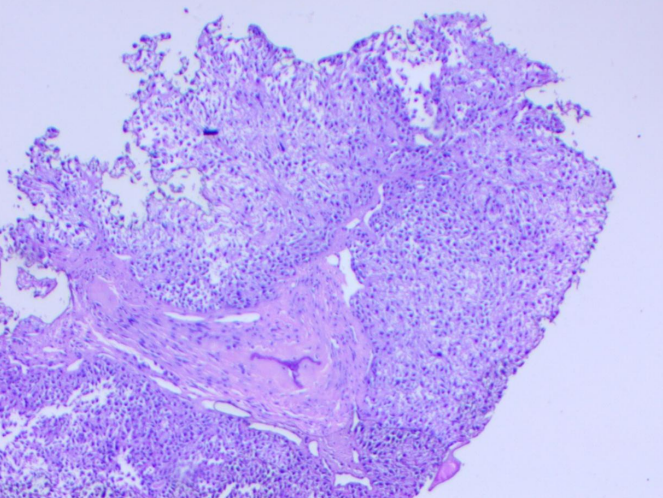

A 71-year-old female presented at Bankers Superspeciality Hospital complaining of swelling over the right side of the face and upper neck region, with localised swelling over the sternum. She was asymptomatic 5 months back as she gradually noticed swelling over her right side of her face and upper neck region, which gradually increased in size. In the past (2018), she had surgery at a local hospital, query for parotid surgery; no documents were available ( surgery note and histopathological report). On inspection and palpation, 8*7cm hard proliferative, lobulated growth present over the right side upper neck region, not fixed to underlying structures, crossing midline of the face with no ulceration present over skin (Image 1). No neck nodes were palpable. No sign of facial palsy present. Localised mass of 6*5cm was present over the right side sternum, which was fixed to the underlying bone (Image 2). No skin ulceration was present over sternum region and no axillary nodes were palpable. The performance status of the patient was ECOG 1. Computed tomography of Neck and chest (Plain + Contrast) suggestive of large heterogeneously enhancing lobulated solid cystic lesion seen in right submandibular and upper internal jugular regions and right submental region anterior to right sternocleidomastoid muscle, size of 94(W)*76(AP)*79.6(CC)mm, with mild compression on right IJV. Approx 78*75*92mm soft tissue lesion involving sternum causing osteolytic destruction extending into the anterior mediastinum displacing heart and other structures posteriorly. A few variable-sized soft tissue density nodules scattered throughout both lungs (Image 3 & Image 4). Trucut Biopsy from Right submandibular region s/o pleomorphic adenoma ( composed of epithelial tubules and myoepithelial cells in abundant chondromyxoid stroma) (Image 5 & Image 6). Trucut Biopsy from sternal mass suggestive of malignant tumor, likely to be sarcoma, chondrosarcoma is a possibility. Further Immunohistochemistry was done which suggestive of lesional cells with chondroid type appearance and matrix with positive for AE1/3, CK7 and S100 with KI-67 2-3% favouring Benign metastasizing pleomorphic adenoma (Image 7 & Image 8). PETCT scan was done, which suggestive of FDG avid heterogenously enhancing lobulated soft tissue mass involving right submandibular and submental region 8.6(AP)*7.3(TS)*8.9(CC) ; SUV max 8.6. Medially involving the Right submandibular gland Indenting onto right SCM and strap muscles, Superioly lesion is infiltrating inferior lobe of right parotid gland, overlying skin is involved with no obvious erosion. FDG avid lytic destructive lesion are noted involving sternum, left fifth rib, D12 and L3 vertebrae. Sternal lytic destructive lesion is present with soft tissue compenent with calcification of 8.2*7.2*10.5cm; SUV max 5.9. Soft tissue component is extending into anterior mediastinum and is seen infiltrating right middle lobe lung parenchyma. Left fifth rib is assosciated with  FDG avid enhancing soft tissue component 2.6*2.3cm; SUVmax 6.5 (Figure 9). On PETCT Scan report with skeletal metastasis, in multidisciplinary tumor board discussion, the case was discussed and decided to give palliative chemotherapy.

Figure 5: Ductal elements and background chondromyxoid stroma and myoepithelial cells

Figure 6: Bone with background PA